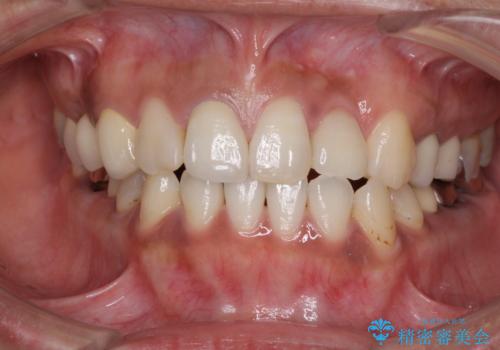

以前治療した歯が続々とむし歯に 全顎むし歯治療

- 歯を削る量が少ないとの触れ込みで最近接着ブリッジを装着したものの、そのブリッジと歯の間に隙間ができているとのことで来院された患者様です。

歯の裏側を一層だけ削り、接着力に頼ったブリッジを装着してはみたものの、案の定咬む力に負けて、接着が剥がれてしまっていました。

前歯の裏側の接着面は、隙間ができていたことにより、汚れがたまるだけでなく、むし歯にもなっていました。